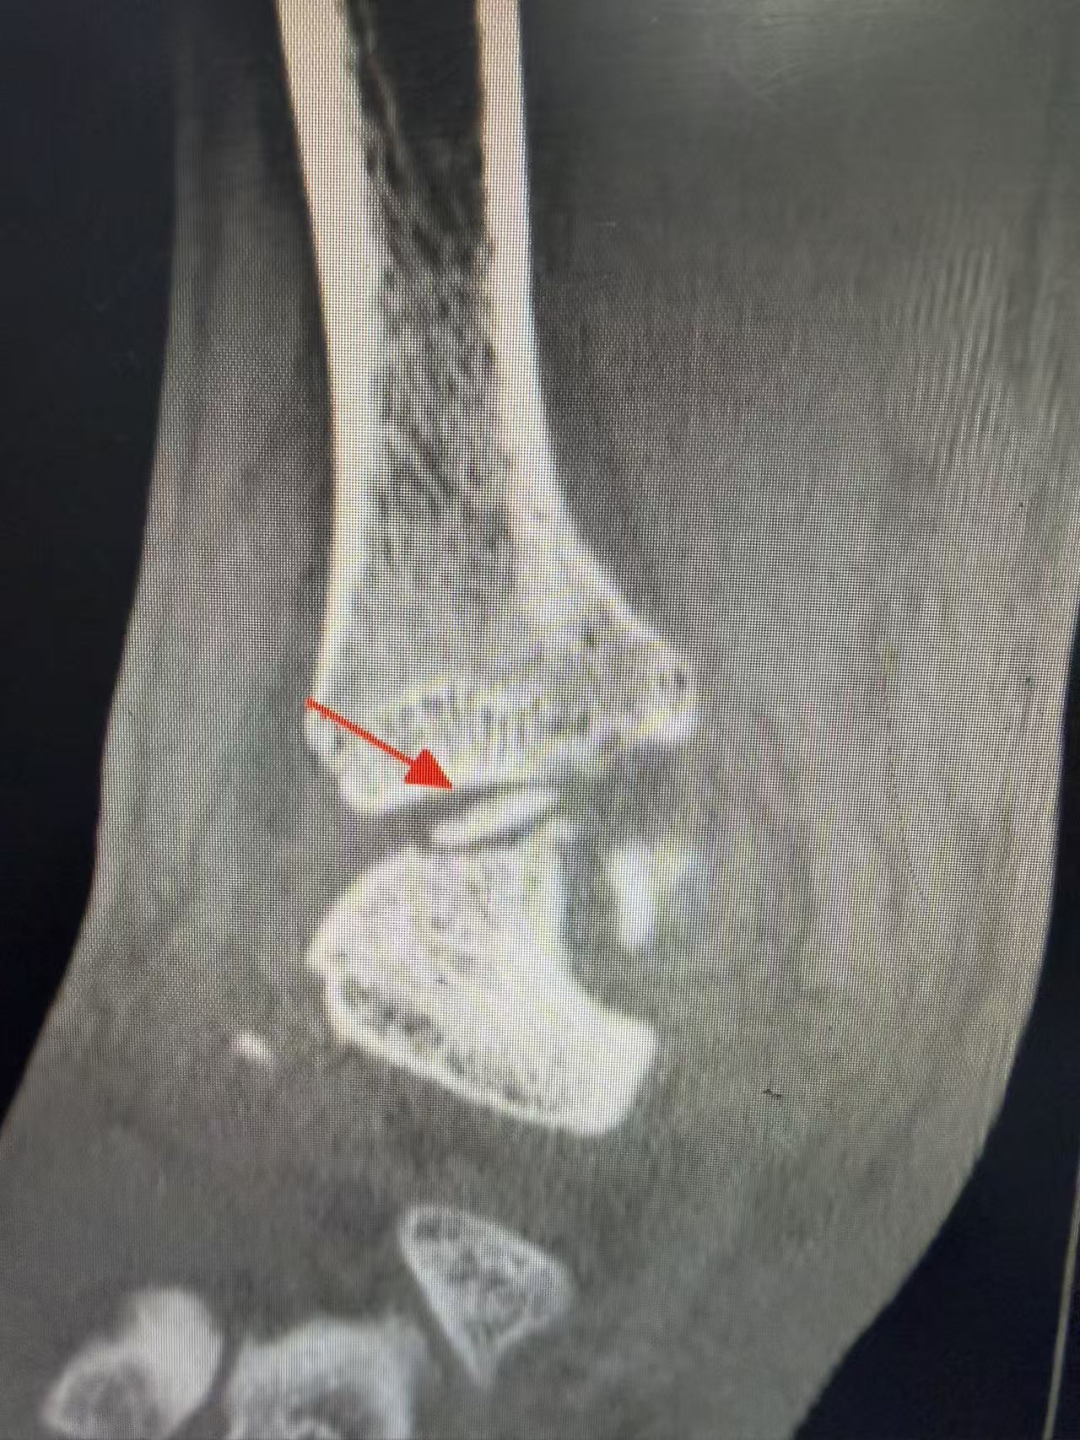

术前影像学检查 踝关节正位片

术前影像学检查 踝关节侧位片